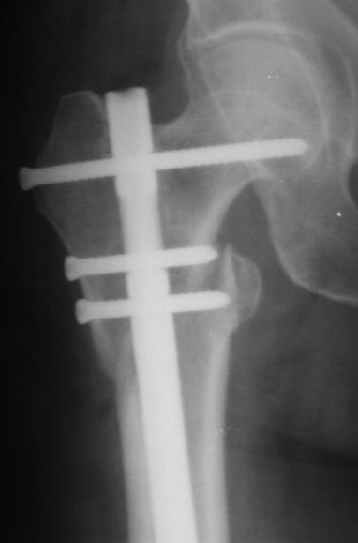

В частности, на проксимальном конце сделано еще одно дополнительное статическое отверстие. Можно ввести в проксимальном отделе 4 винта, из них 3 статические (2 в круглые отверстия и 1 по нижнему краю овального). Картинки в приложении. На дистальном конце стержня тоже кое-что улучшено. Спрашивайте в аптеках, как говорится. Выпускается предприятием "ЦИТО" (Москва), то есть это малобюджетное решение.

Конечно, мы не синтезируем остеопорозые вертельные переломы согласно прилагаемому примеру, винты 6 мм вырежутся. Но у более молодых при хорошем качестве кости такие или подобные гвозди с поперечным расположением винтов вполне применимы для меж- и подвертельных переломов.

Это было года 2,5 назад, мы тогда еще уточняли возможности шинирования с угловой стабильностью гвоздем с поперечным расположением винтов при переломах проксимального отдела бедра. Пациенту не пришлось приобретать намного более дорогой рекон или проксимальный гвоздь. В приложении еще несколько примеров применения того гвоздя при высоких переломах бедра, в том числе с более латеральной точкой входа. Гвоздь изгибаем для этого.